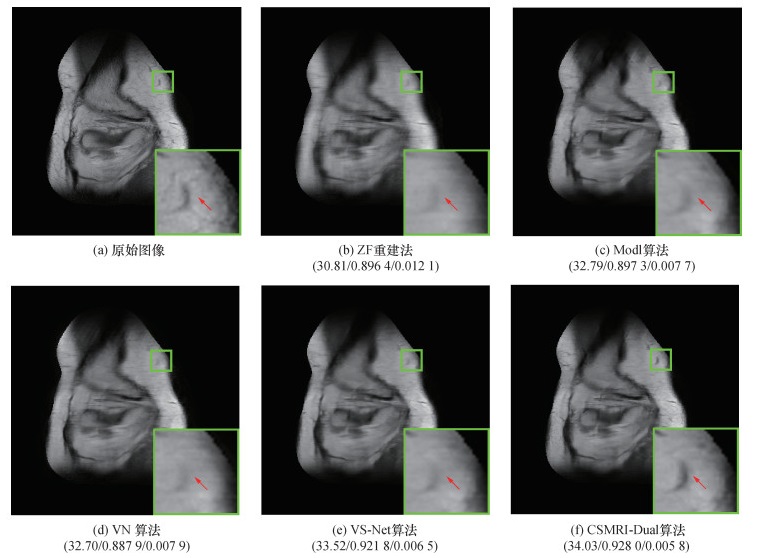

为进一步评估本文提出的CSMRI-Dual算法的重建效果,图 2和图 3分别展示了在4倍和6倍AF时,不同算法重建图像的区域放大图。由图可知,ZF重建图像非常模糊,并且图像过于平滑,缺少细节信息;Modl算法恢复出的重建图像同样丢失了很多的细节信息;VN算法和VS-Net算法重建图像类似,比Modl算法恢复出的重建图像有明显提升,但是细节信息依旧有部分丢失;CSMRI-Dual算法重建图像在4倍AF下视觉效果较好,有效消除了噪声,获得了更多细节,且保留了丰富的纹理信息;在6倍AF下,重建细节更接近原始图像,重建图像较为清晰。由此可见,CSMRI-Dual算法表现出了良好的重建效果。

| 图 2 4倍AF下不同算法重建图像的对比(平均PSNR/SSIM/NMSE) |